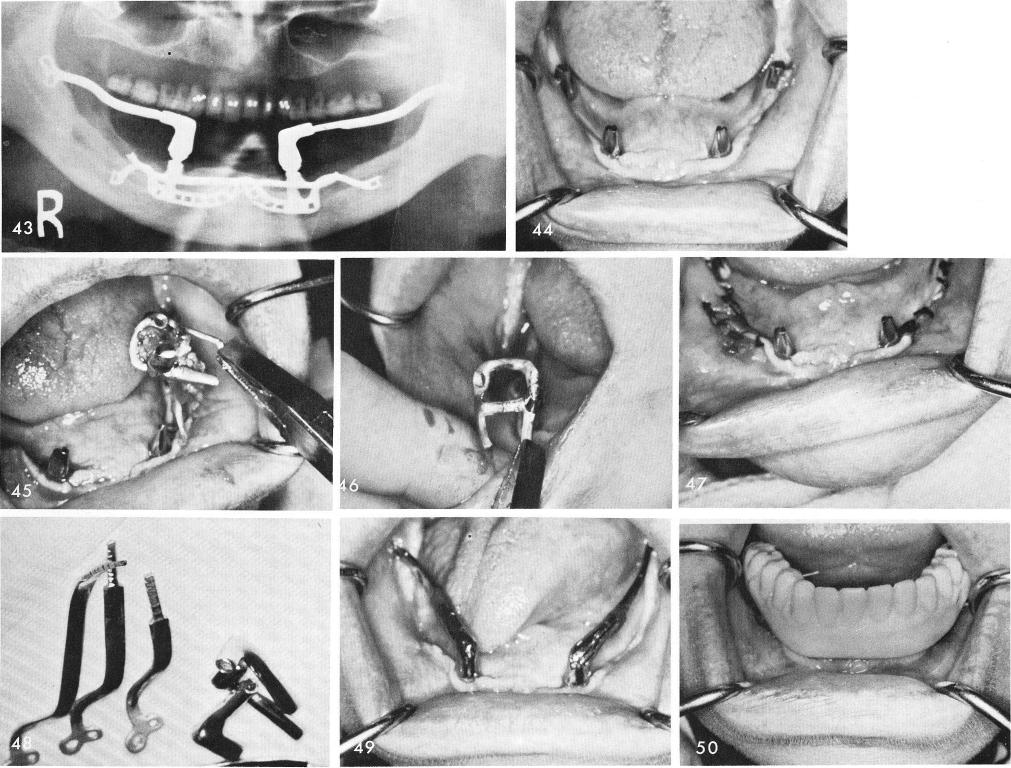

lent, fig. 49. The patient had been wearing this cold cured temporary acrylic splint immediately after surgery, fig. 50. The final denture is locked over the ramus implant with Duralay, fig. 51, and the final occlusion is adjusted, fig. 52. The post-operative x-ray, figs. 53, 54.

1 Failing subperiosteal mandibular implant